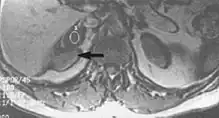

Slice-to-slice interference

Fig. 11. Slice-to-slice interference (T1 axial study of lumbar vertebrae).[1]

Non-uniform RF energy received by adjacent slices during a multi-slice acquisition is due to cross-excitation of adjacent slices with contrast loss in reconstructed images (Fig. 11). To overcome these interference artifacts, the acquisition of two independent sets of gapped multi-slice images need to be included, and subsequently reordered during display of the full image set.[1]